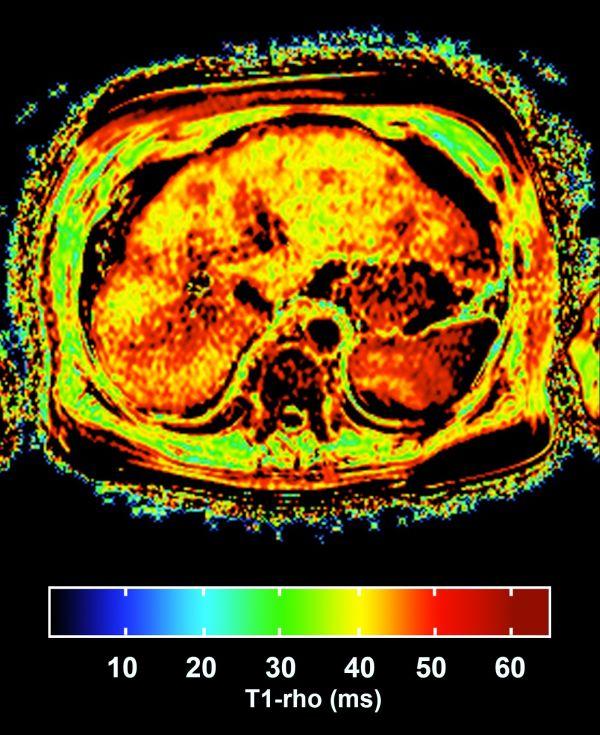

Zu den Weiterentwicklungen der letzten Jahre zählen unter anderem innovative Verfahren zur nicht-invasiven, farbkodierten Bildgebung und quantitativen Analyse der Flusseigenschaften des zerebro-spinalen Liquors Auch bei der Diagnostik und Verlaufskontrolle entzündlicher und tumoröser Erkrankungen des zentralen Nervensystems haben sich die Möglichkeiten der MR erweitert. Beides kommt zur Sprache bei dem Fachtreffen, das das Institut für Klinische Radiologie (IKR) des Universitätsklinikums Münster in Zusammenarbeit mit der Akademie für Fort- und Weiterbildung in der Radiologie ausrichtet. Neben institutseigenen Referenten konnten die Organisatoren mehrere international bekannte Experten für das Symposium gewinnen, das auf interaktive Wissensvermittlung setzt.